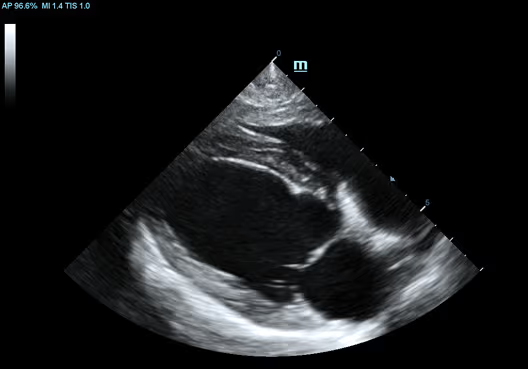

Köpek Kalbinin Uzun Eksen Görünümü

Köpek Kalbinin Uzun Eksen Görünümü